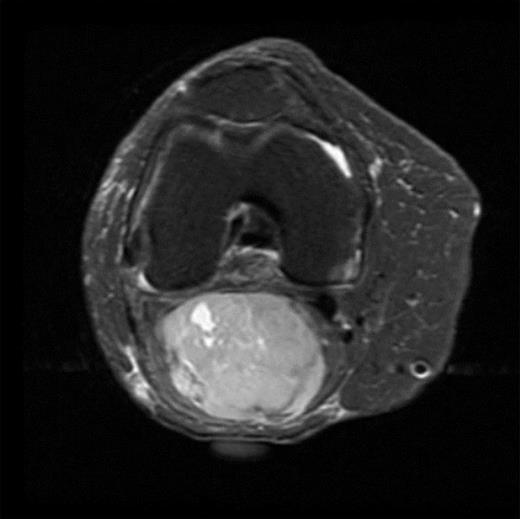

The MRI scan of the right knee (Figs 2 and 3) with gadolinium-enhancement showed a large mass lesion in the posterior aspect of the right knee extending into the popliteal fossa and into the upper third of the right leg having appearance of bursal pathology. Post gadolinium images showed evidence of circumferential rim enhancement but no internal enhancement indicating the presence of a fluid filled lesion. The mass (Figs 4 and 5) measured ∼8.39 × 6.14 × 12.72 cm and was seen between semimembranosus and biceps femoris muscles. There was no evidence of any infiltration of either the sciatic nerve or the popliteal vessels. A likely diagnosis of complicated synovial cyst with a differential diagnosis of haematoma was reported and a provisional diagnosis of Baker's cyst was established.

Post gadolinium-enhanced MRI image showing circumferential lesion.